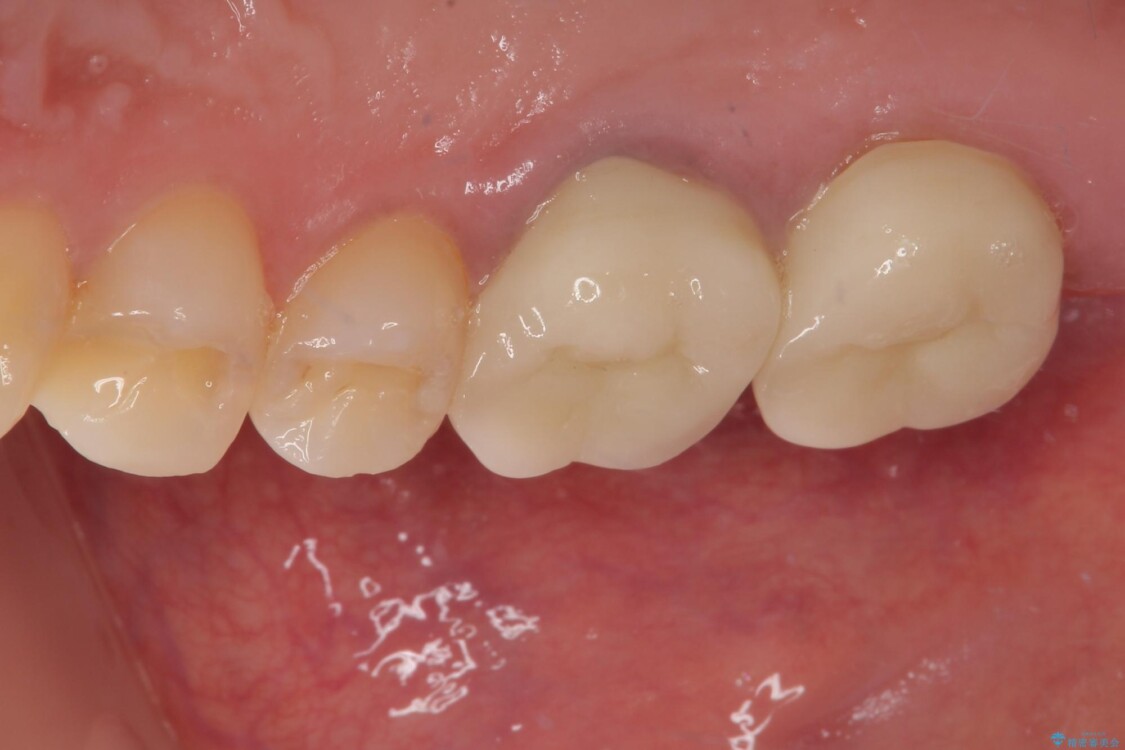

スペースが整った段階で、右下の第一大臼歯と第二大臼歯にインプラントを埋入。

その後、挺出していた右上第一大臼歯と第二大臼歯に装着されていた銀歯についても、審美性と適合性の向上を目的に、オールセラミッククラウンにやり替えました。

これにより、より自然で美しい見た目と、高い精度の咬合が得られています。

治療後

• 挺出歯を圧下してスペースを確保!目立たない部分矯正で下顎大臼歯にインプラント治療を実現 治療後画像